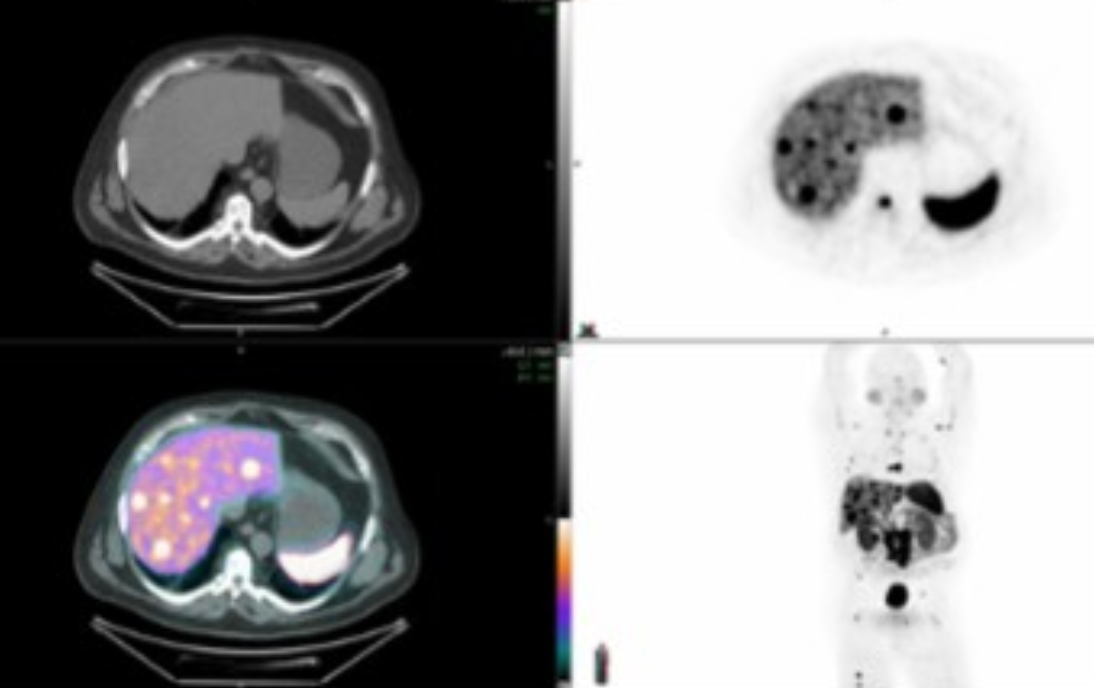

• What is PET good at vs MR and Contrasted CT

• Solid organ mets —> PET is best

• Vascular invasion and peritoneal carcinomatosis —> CECT is best